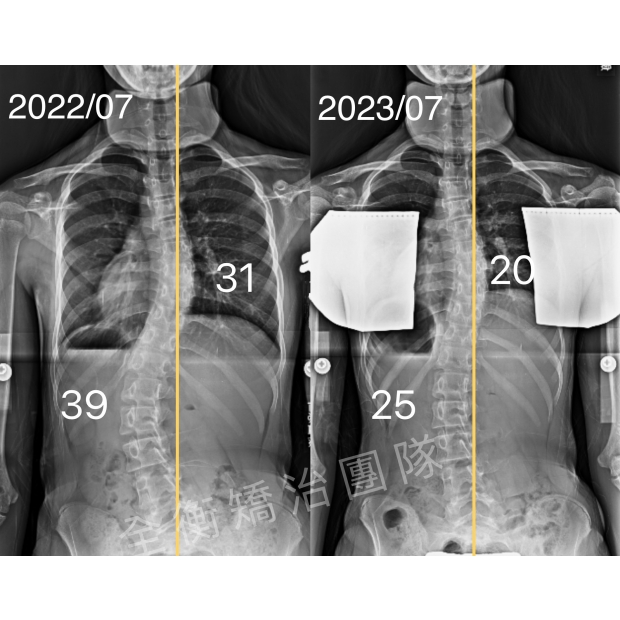

11歲側彎女孩,兩年,腰彎從35度進步到16度11歲側彎女孩,兩年,腰彎從35度進步到16度

女孩11歲發現側彎,當時胸彎38度,腰彎35度,

惡化風險100%,但骨齡為0,正處黃金矯治期,

兩年時間,腰彎從35度進步到16度,

體態平衡從原本嚴重左偏到現在較為回正,

腰椎旋轉也明顯進步 -